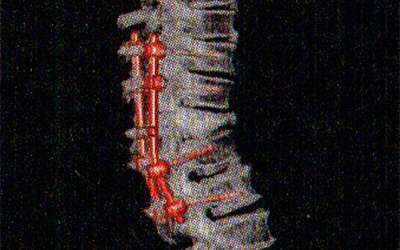

神経を圧迫している部分の骨を取り除く除圧術、不安定な脊椎や狭窄の進んだ脊椎を固定する固定術、外傷によって傷ついた脊椎の再建術などがあります。ナビゲーションシステムと手術中CTを用いて低侵襲(きずが目立ちにくい)で正確な手術を行っています。脳と脊椎は切っても切れない関係です。

胸椎破裂骨折に対する固定術